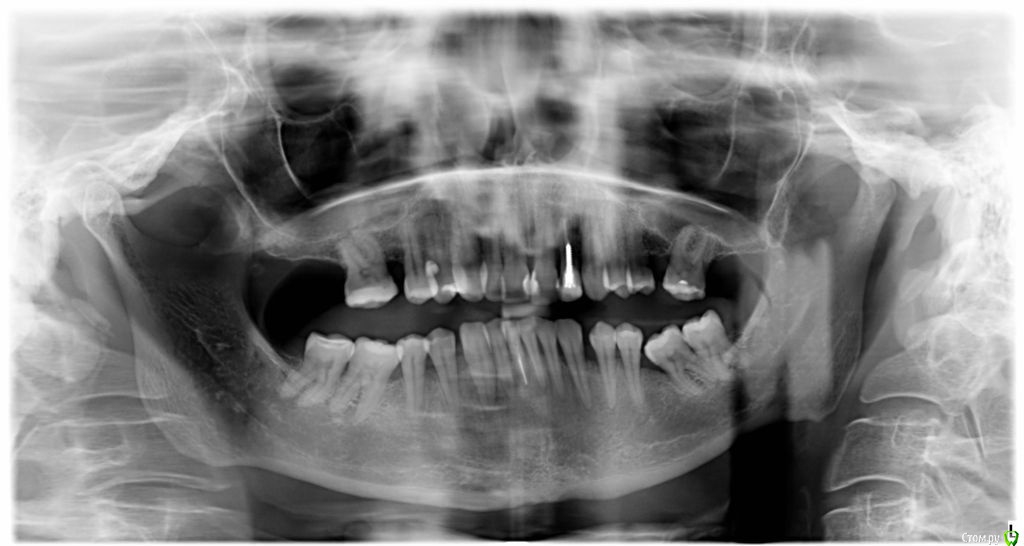

VVQW Опубликовано 6 декабря, 2016 Поделиться Опубликовано 6 декабря, 2016 В результате некачественной ортодонтии более 10 лет назад имеется такая картина. Посоветуйте что-можно сделать?Верхние 6-ки удалены перед брекет системой, по решению ортодонта. Верхние 8-ки не выросли, нижние 6-ки - удалены в подростковом возрасте до 14 лет. http://s019.radikal.ru/i639/1612/56/1345f17db908.jpg http://s019.radikal.ru/i630/1612/55/145ef7c813b2.jpg http://s017.radikal.ru/i440/1612/c2/74bd4da2643e.jpg http://s008.radikal.ru/i303/1612/b4/e80683ed7d2b.jpg http://s010.radikal.ru/i314/1612/74/6d2f9671b0d5.jpg http://s018.radikal.ru/i502/1612/97/9a15fcf4ddd3.jpg http://s020.radikal.ru/i715/1612/59/9bb4a006621f.jpg Ссылка на комментарий

VVQW Опубликовано 6 декабря, 2016 Автор Поделиться Опубликовано 6 декабря, 2016 Добрый день. Беспокоят клиновидки и их прогрессирование из-за неправильной окклюзии.Которая из-за неккоректно проведенного ортодонтическлго лечения. Одно из мнений ортодонтов, 50/50, что надо провести повторное лечение и восстановить зубной ряд имплантами. Вот только дальше варианты у всех свои. Если в верху подвинуть 7 к 5, есть место для импланта? Кость позволит? И наоборот если сделать место под 6, можно ли туда импоант поставить? Спасибо. Ссылка на комментарий